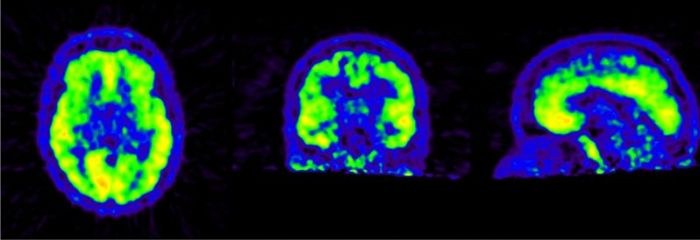

Im Rahmen unserer Studien führen wir z. B. funktionelle Untersuchungen des Gehirns mittels der Positronen-Emissions-Tomographie (PET, Dauer ca. 1,5 Stunden) sowie anatomische und funktionelle Untersuchungen mittels Magnetresonanztomographie (MRT, Dauer ca. 10 Minuten) durch. Je nach Studie werden auch weitere Zusatzuntersuchungen wie z. B. EEG, neuropsychologische Testungen etc. durchgeführt. Die Gesamtdauer der Untersuchungen beläuft sich in der Regel auf etwa 3 – 4 Stunden.